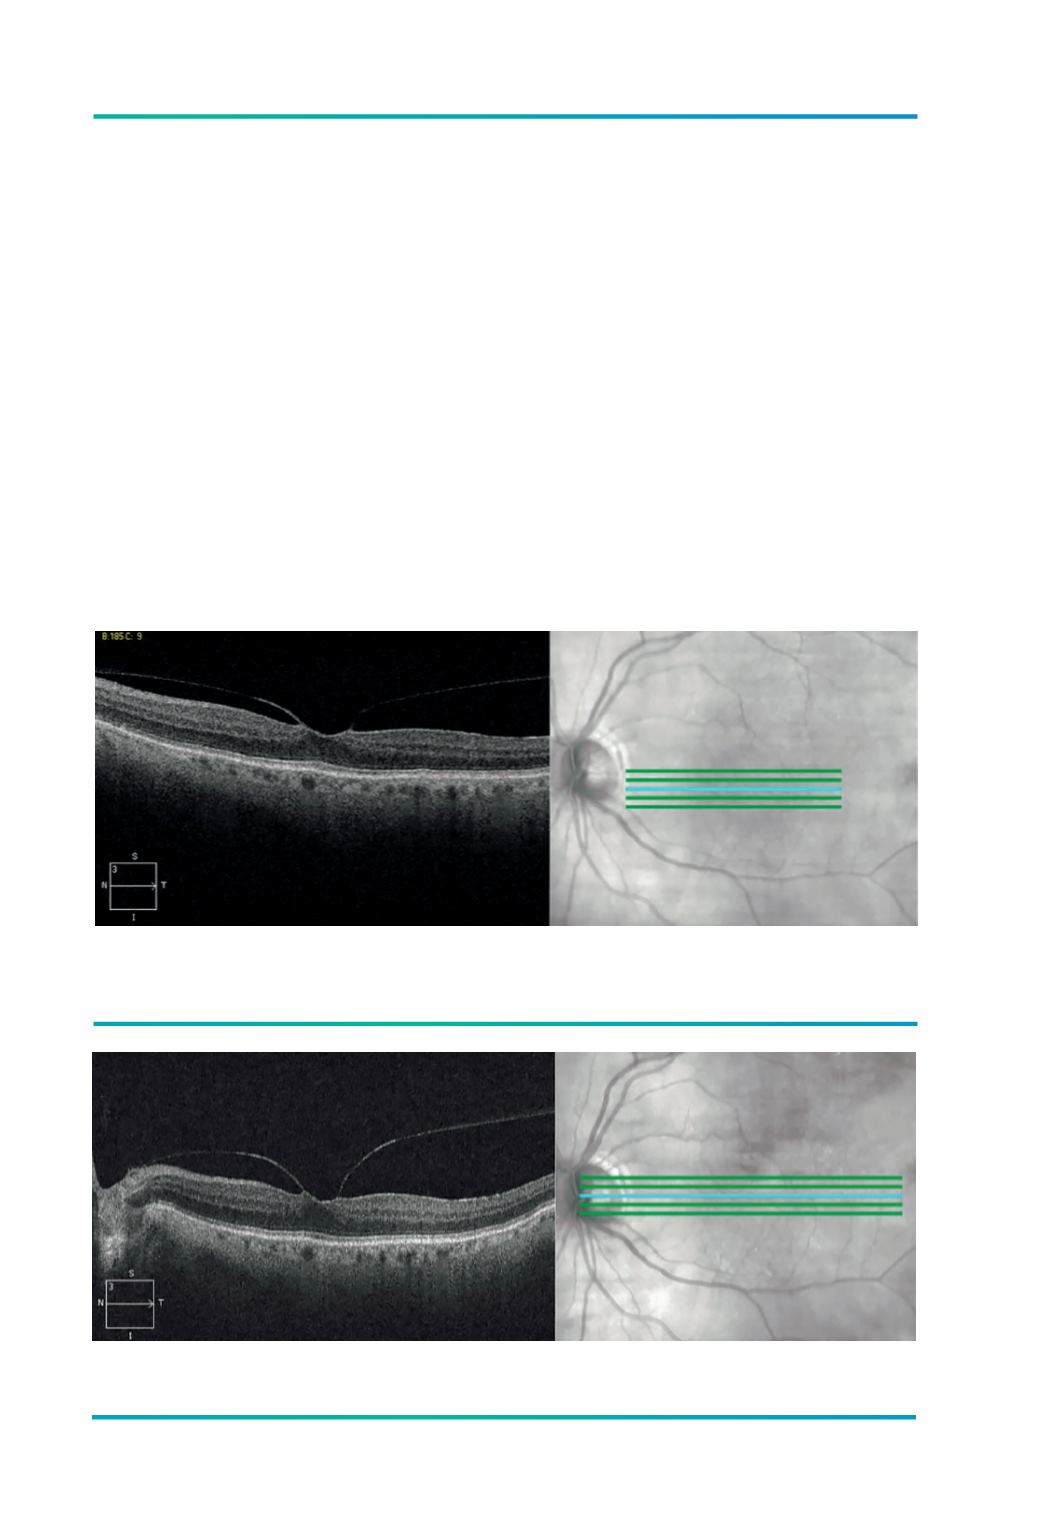

Figura 2.

Raster scan 6 mm.

Figura 3.

Raster scan 9 mm.